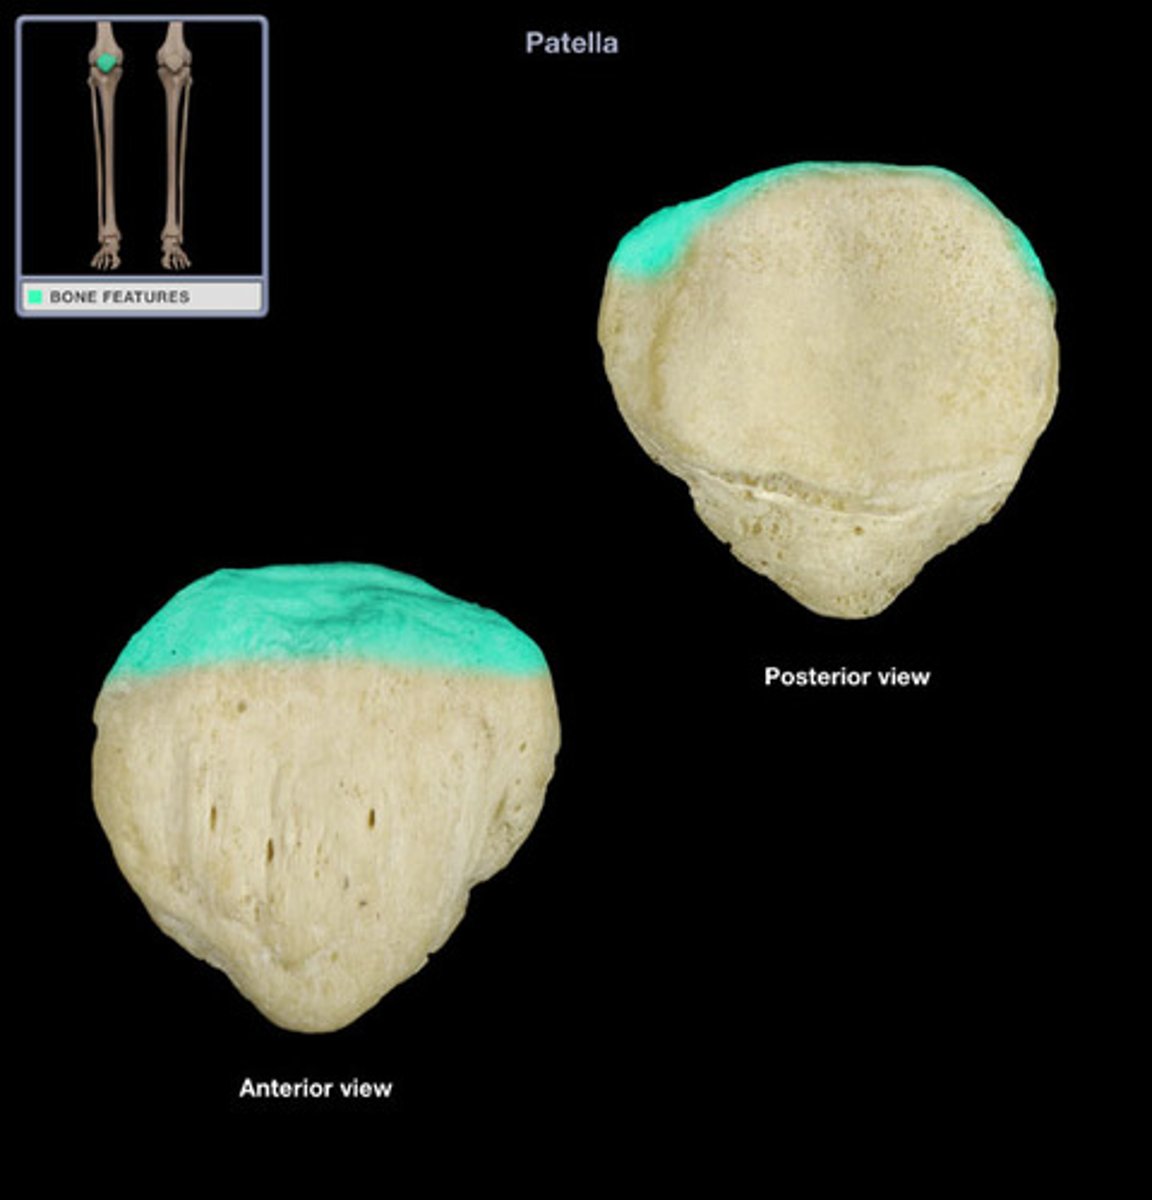

Patella

Base

superior surface for quadriceps tendon